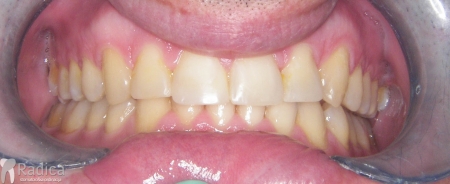

Slučaj 1: ispravljanje otvorenog zagriza i kompresije Invisalign full terapijom

Slučaj 2: ispravljanje kompresije Invisalign full terapijom- u ovom slučaju je izvađen jedan donji sjekutić

Slučaj 3: ispravljanje kompresije Invisalign full terapijom

Slučaj 4: ispravljanje kompresije Invisalign full terapijom

Slučaj 5: ispravljanje kompresije i križnog zagriza Invisalign full terapijom

Slučaj 6: ispravljanje kompresije i dubokog zagriza Invisalign full terapijom

Slučaj 7: ortodontska predprotetska terapija Invisalign full